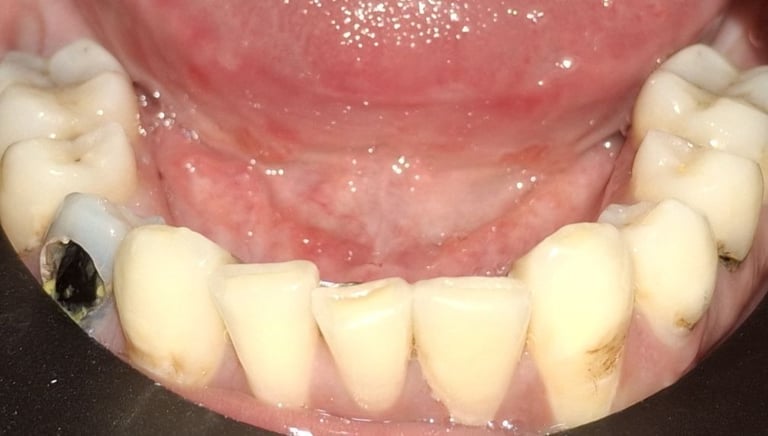

Clinical pictures of teeth requiring RCT

All images are of real cases of teeth where Root canal treatment was performed to remove infection and preserve the natural tooth restoring normal chewing and function of teeth.